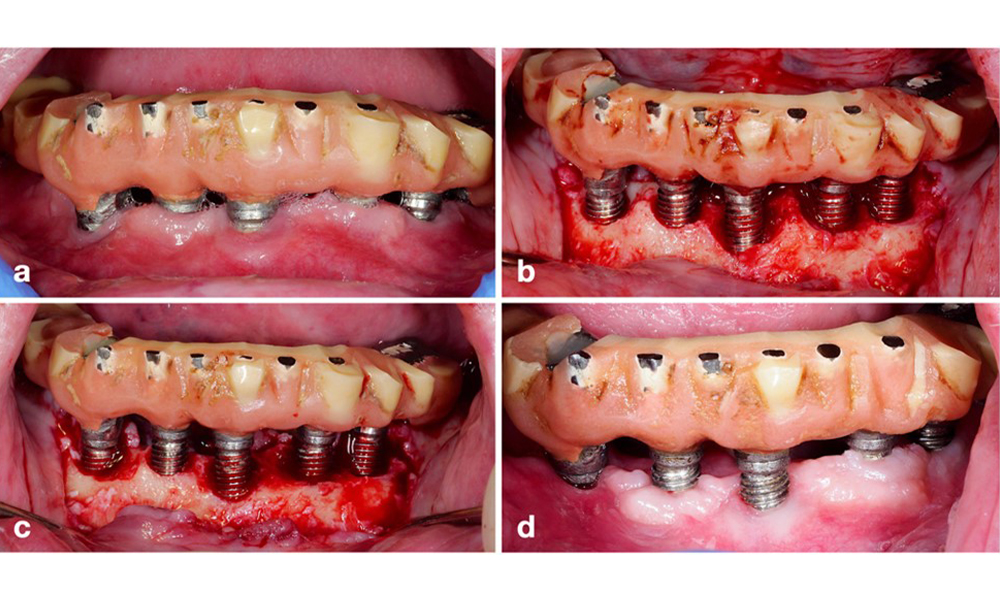

Основният етиологичен фактор за биологичните усложнения около имплантите е оралният биофилм. Ето защо по време на лечението винаги трябва да се вземат предвид два съществени аспекта, независимо от диагнозата периимплантатен мукозит или периимплантит: (1) нивото на орална хигиена и (2) възможността за почистване на протезното възстановяване (фигура 4).

Възстановяване на цяла дъга на долна челюст със значително натрупване на плака поради лоша орална хигиена. Обърнете внимание на голямото разстояние между букалната страна на протезата и имплантите от дясната страна (бели стрелки).

Фигура 4. Възстановяване на цяла дъга на долна челюст със значително натрупване на плака поради лоша орална хигиена. Обърнете внимание на голямото разстояние между букалната страна на протезата и имплантите от дясната страна (бели стрелки).

По този начин както ежедневната орална хигиена на пациента, така и дизайнът на протезното възстановяване и позиционирането на импланта трябва да подпомагат ефективното почистване. Ако е необходимо, корекциите на съществуващата реставрация (фигура 5) и специфични инструкции за персонализирана орална хигиена са от изключителна важност (фигура 6) (Hamilton et al. 2023; Jepsen et al. 2015).

Модификация на съществуващ мост. Ако възстановяването възпрепятства адекватната орална хигиена (забележете крайната протрузия от букалната страна на молара) (a–b), една от първите стъпки на лечение трябва да бъде коригиране на протезния дизайн, за да се позволи ефективно почистване (c–d).

Фигура 5. Модификация на съществуващ мост. Ако възстановяването възпрепятства адекватната орална хигиена (забележете крайната протрузия от букалната страна на молара) (a–b), една от първите стъпки на лечение трябва да бъде коригиране на протезния дизайн, за да се позволи ефективно почистване (c–d).